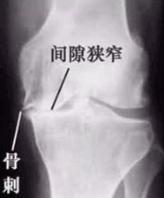

膝关节是承担着人体的大部分重量,运动不当或者受到外伤后,极易出现骨科类疾病。在膝关节出现骨刺后,可能导致疼痛,活动受限,严重影响到患者的正常生活。那么,生活中诱发膝盖骨刺的因素都有哪些呢?

图:膝关节骨刺示意图